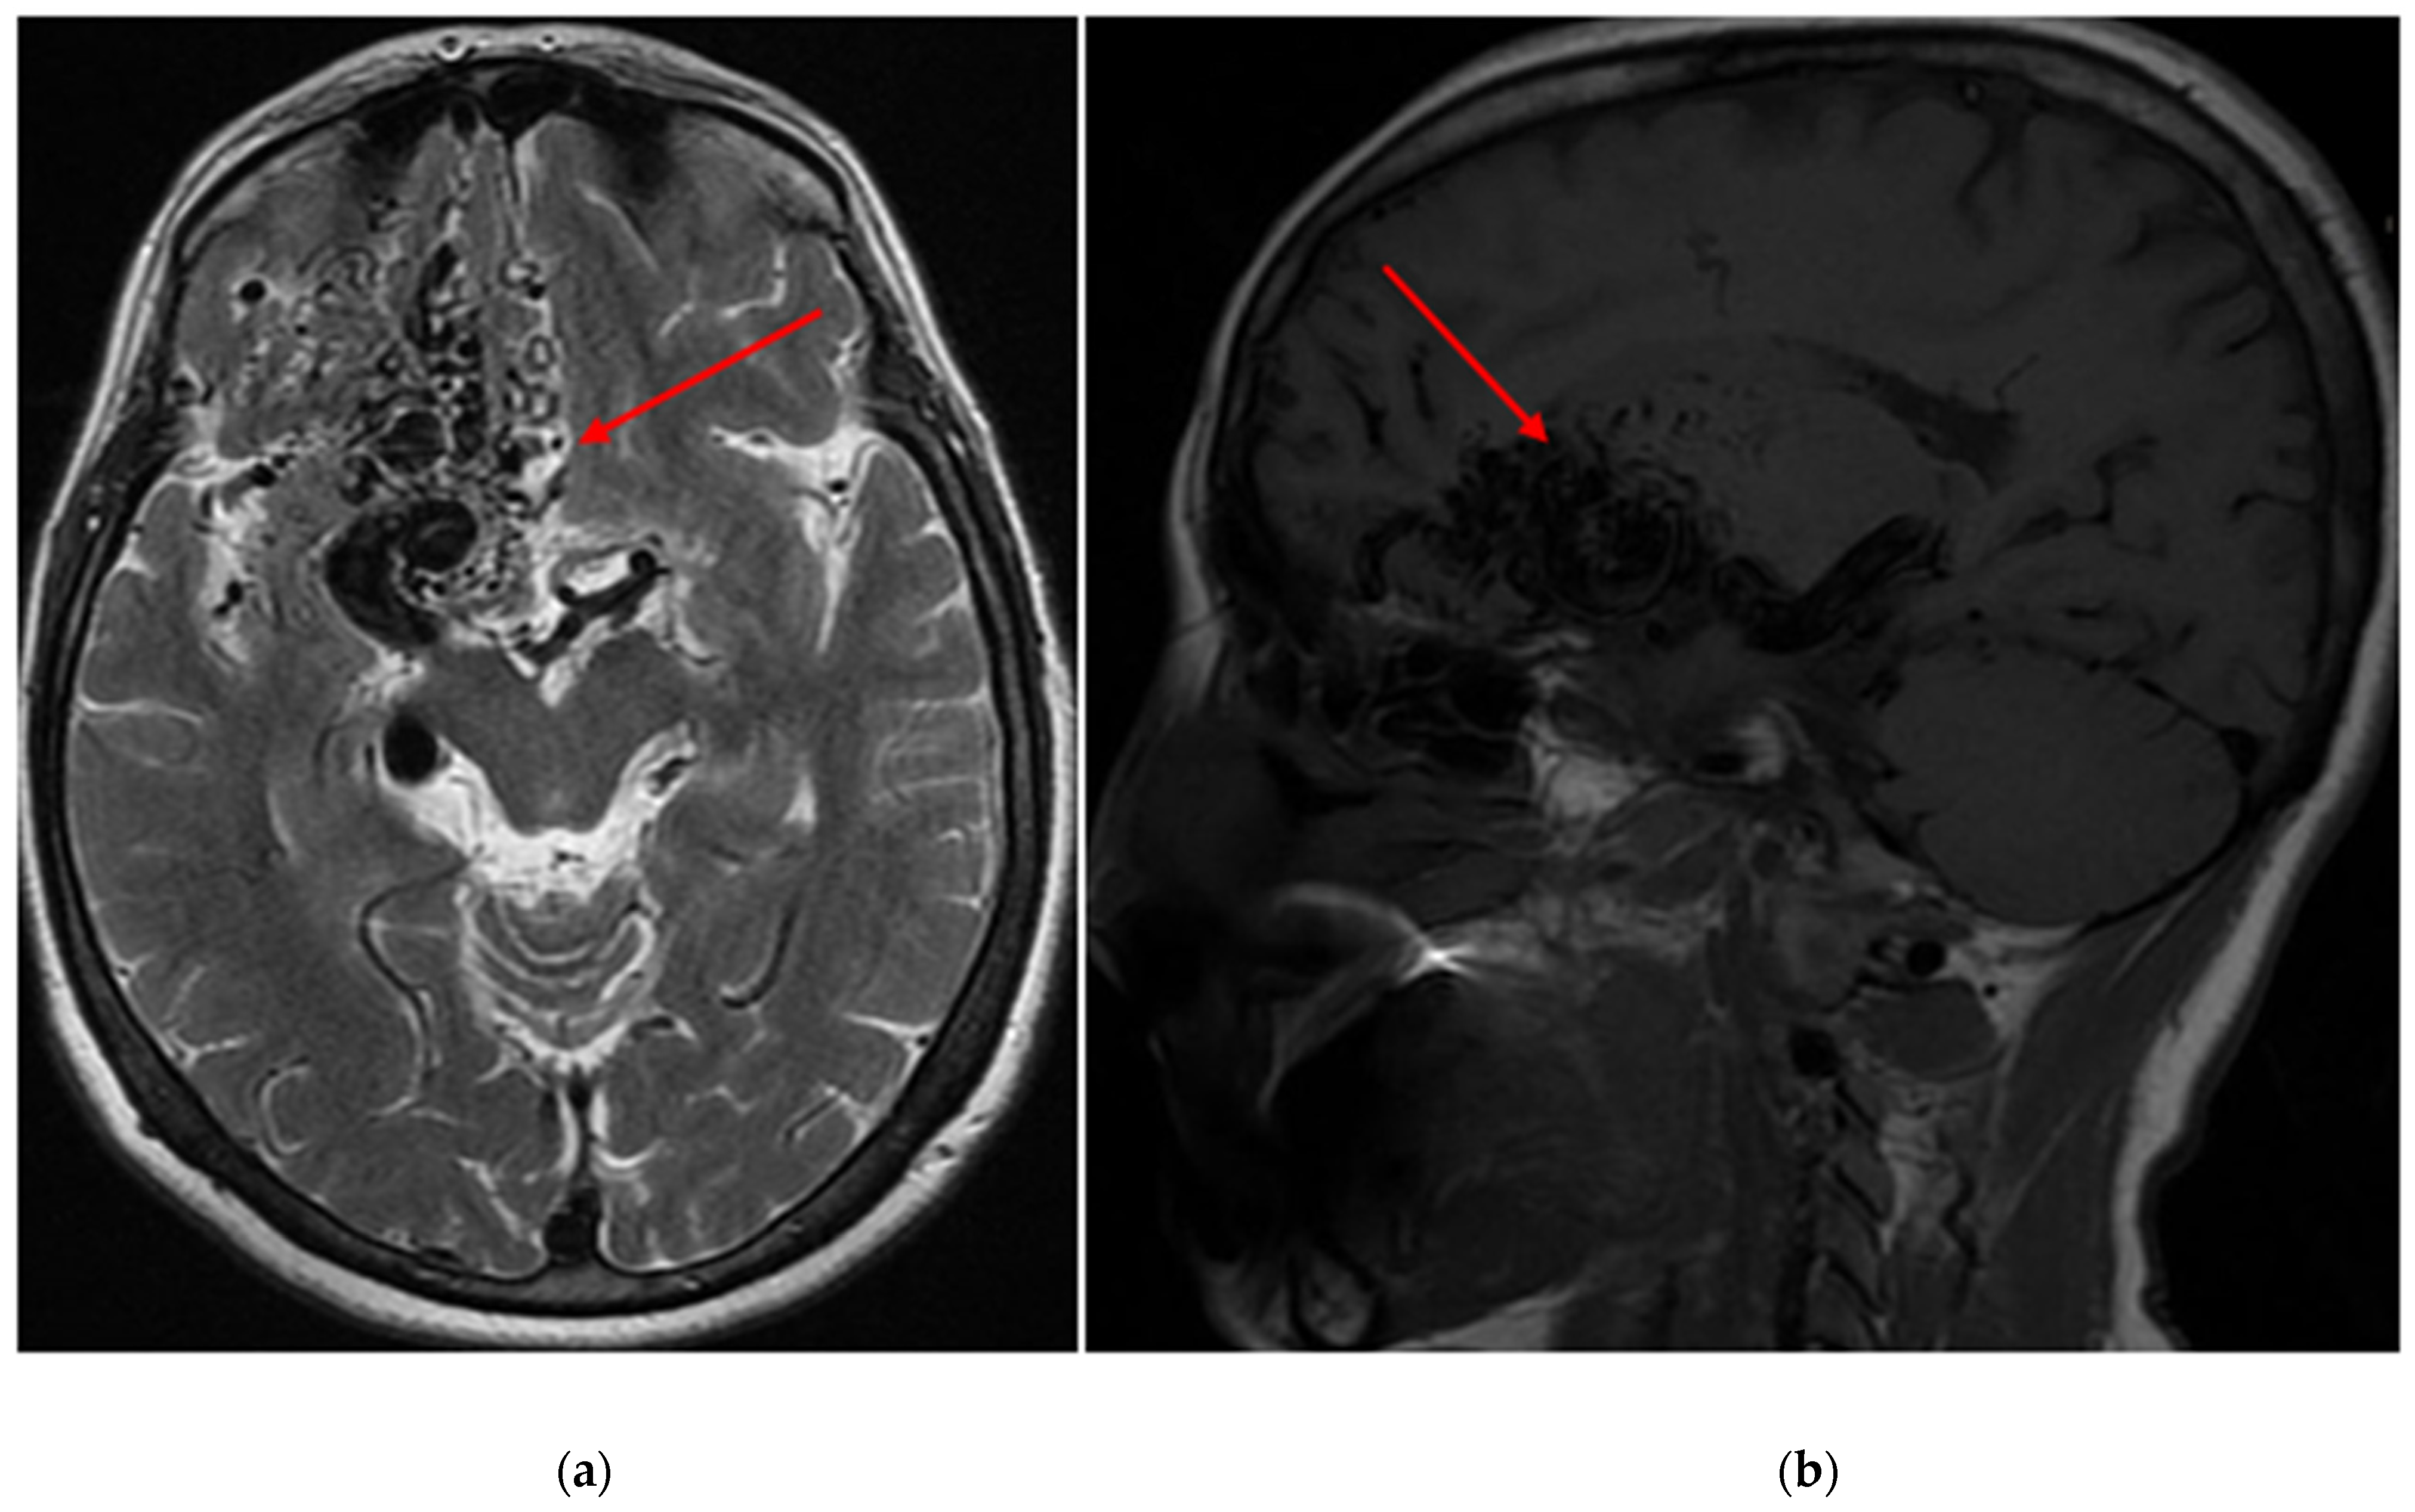

Demographic and clinical data of AVM sampling are shown in Table 1. Seventy patients presented with AVM-associated seizures, and 93 participants had no signs of seizures. Figure 1 and Figure 2 show magnetic resonance imaging (MRI) and cerebral angiography images of the brain of a patient with seizures associated with arteriovenous malformations. In total, 55.71% of subjects with seizures and 56.99% of AVMs without seizures were female. The age and BMI composition of cases and controls were comparable and not statistically significantly different (p > 0.05). Almost 95% of all participants underwent partial or total embolization (Table 2). The most common symptom was rupture, present in 41.98% of all participants.

Figure 1. (a) An axial T2 magnetic resonance image of the brain depicts an arteriovenous malformation (AVM) situated within the right frontal lobe (red arrows), with a Spetzler-Martin grade of IV assigned to it (b) A sagittal T1 magnetic resonance image of the brain reveals the same AVM located within the right frontal lobe, also assigned a Spetzler-Martin grade of IV.